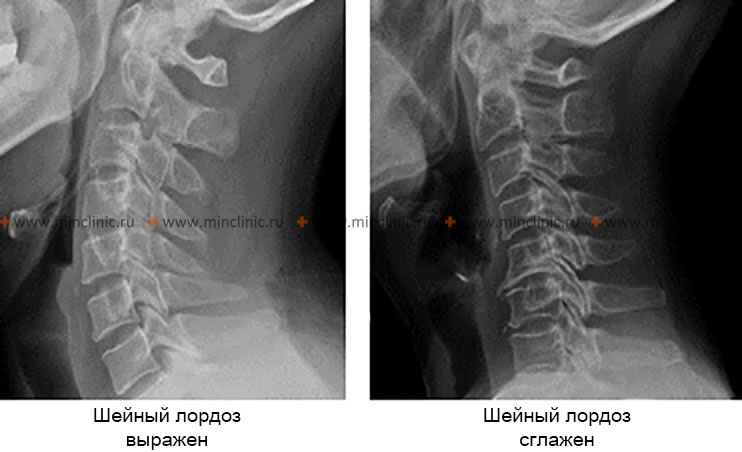

Рентгенография шейного отдела позвоночника в боковой проекции указывает на изменение шейного лордоза (выражен и сглажен).